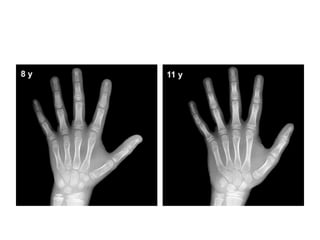

Pre-puberty

• Males: 3 years to 9 years of age

• Assessments of skeletal maturity in pre-pubertal

children are primarily based on the

epiphyseal size of the phalanges as they relate

to the adjacent metaphyses

• During this stage of development, the ossification

centers for the epiphyses increase in width and

thickness, and eventually assume a transverse

diameter as wide as the metaphyses.

• More weight is given to the size of the epiphyses

in the distal phalanges than to that in the middle

phalanges, and even less to that in the proximal

phalanges

Early and Mid-puberty

• Males: 9 years to 14 years of age

• As in pre-pubertal children, assessments of skeletal

maturity in early and mid-puberty are also based on

the size of the epiphyses in the distal phalanges (first)

and the middle phalanges (second).

• The epiphyses at this stage continue to grow and their

widths become greater than the metaphyses

• Thereafter, the contours of the epiphyses begin to

overlap, or cap, the metaphyses. This capping effect

is depicted in a two-dimensional radiograph as small

bony outgrowths, like tiny horns, on both sides of

the shaft.

Pre-puberty • Females:2 years to 7 years of age • Males: 3 years to 9 years of age • Assessments of skeletal maturity in pre-pubertal children are primarily based on the epiphyseal size of the phalanges as they relate to the adjacent metaphyses

• During thisstage of development, the ossification centers for the epiphyses increase in width and thickness, and eventually assume a transverse diameter as wide as the metaphyses. • More weight is given to the size of the epiphyses in the distal phalanges than to that in the middle phalanges, and even less to that in the proximal phalanges

Early and Mid-puberty • Females: 7 years to 13 years of age • Males: 9 years to 14 years of age • As in pre-pubertal children, assessments of skeletal maturity in early and mid-puberty are also based on the size of the epiphyses in the distal phalanges (first) and the middle phalanges (second). • The epiphyses at this stage continue to grow and their widths become greater than the metaphyses

• Thereafter, thecontours of the epiphyses begin to overlap, or cap, the metaphyses. This capping effect is depicted in a two-dimensional radiograph as small bony outgrowths, like tiny horns, on both sides of the shaft. • The pisiformand the sesamoid in the tendon of the abductor pollicis, just medial to the head of the first metacarpal, become recognizable during puberty. • However, these centers, as well as those of the other carpals and metacarpals, are less reliable as indicators of bone age at this stage of development.